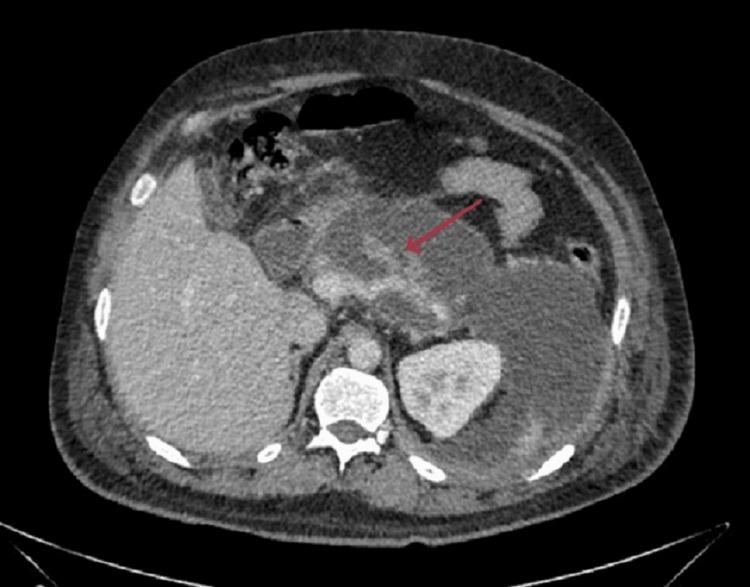

Acute pancreatitis (AP) is an inflammatory condition with varied clinical presentations. Local complications include peripancreatic fluid collection, acute necrotic collection, walled-off necrosis, and pancreatic pseudocyst, but vascular complications like pseudoaneurysm and venous thrombosis are also reported. Patients often experience splanchnic venous thrombosis, which can affect the splenic vein, portal vein, and superior mesenteric vein individually or in combination. Rarely, extra-splanchnic venous thrombosis, including renal vein, superior vena cava, and inferior vena cava thrombosis, has been reported in cases of chronic pancreatitis. The formation of a venous thrombus in acute pancreatitis is multifaceted, with pancreatic inflammation and the immune response mounted by the patient playing a significant role. There is a dearth of medical literature regarding extra-splanchnic venous thrombosis and the use of therapeutic anticoagulation in the successful treatment of the above-mentioned complication. This case report highlights the rare complications that can be seen in cases of acute pancreatitis.

急性胰腺炎(AP)是一种临床表现多样的炎症性疾病。局部并发症包括胰周液体积聚、急性坏死性积聚、包裹性坏死和胰腺假性囊肿,但也有报道称存在诸如假性动脉瘤和静脉血栓形成等血管并发症。患者常发生内脏静脉血栓形成,可单独或联合累及脾静脉、门静脉和肠系膜上静脉。在慢性胰腺炎病例中,罕见报道有包括肾静脉、上腔静脉和下腔静脉血栓形成在内的内脏外静脉血栓形成。急性胰腺炎中静脉血栓的形成是多方面的,胰腺炎症和患者的免疫反应起了重要作用。关于内脏外静脉血栓形成以及使用治疗性抗凝剂成功治疗上述并发症的医学文献较少。本病例报告突出了急性胰腺炎病例中可能出现的罕见并发症。